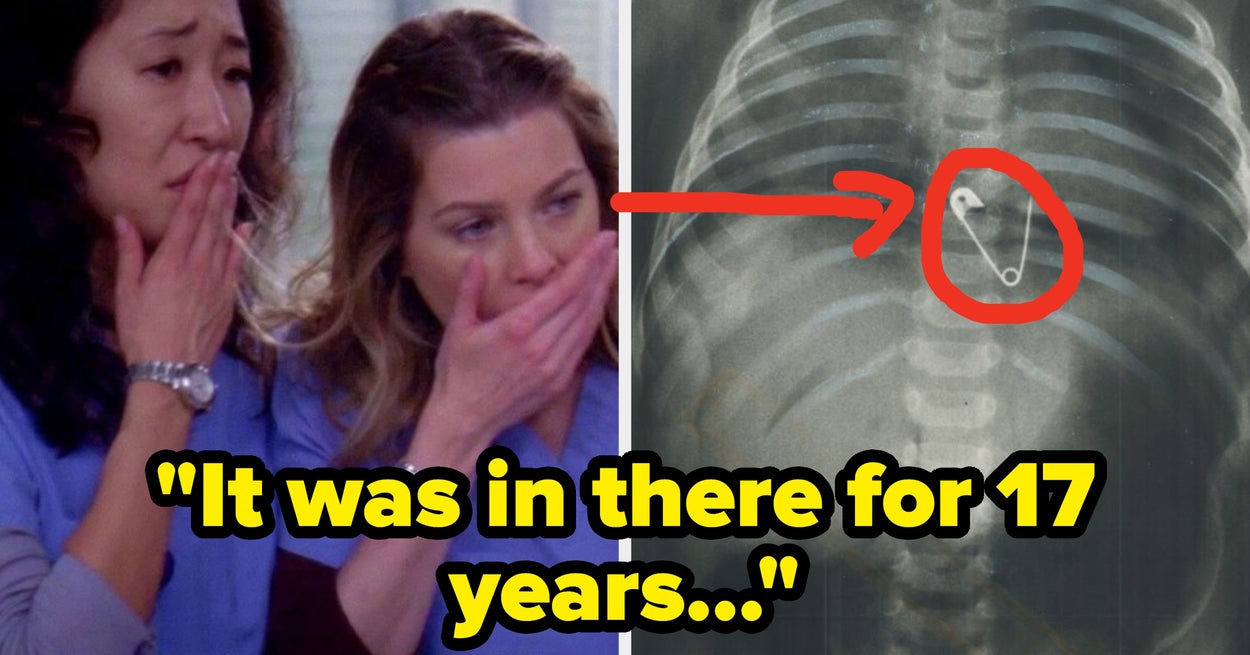

Surgeons, What's The Most Jaw-Dropping Thing You've Seen In The OR?

Be honest, is it actually wilder than Grey’s Anatomy? 👀